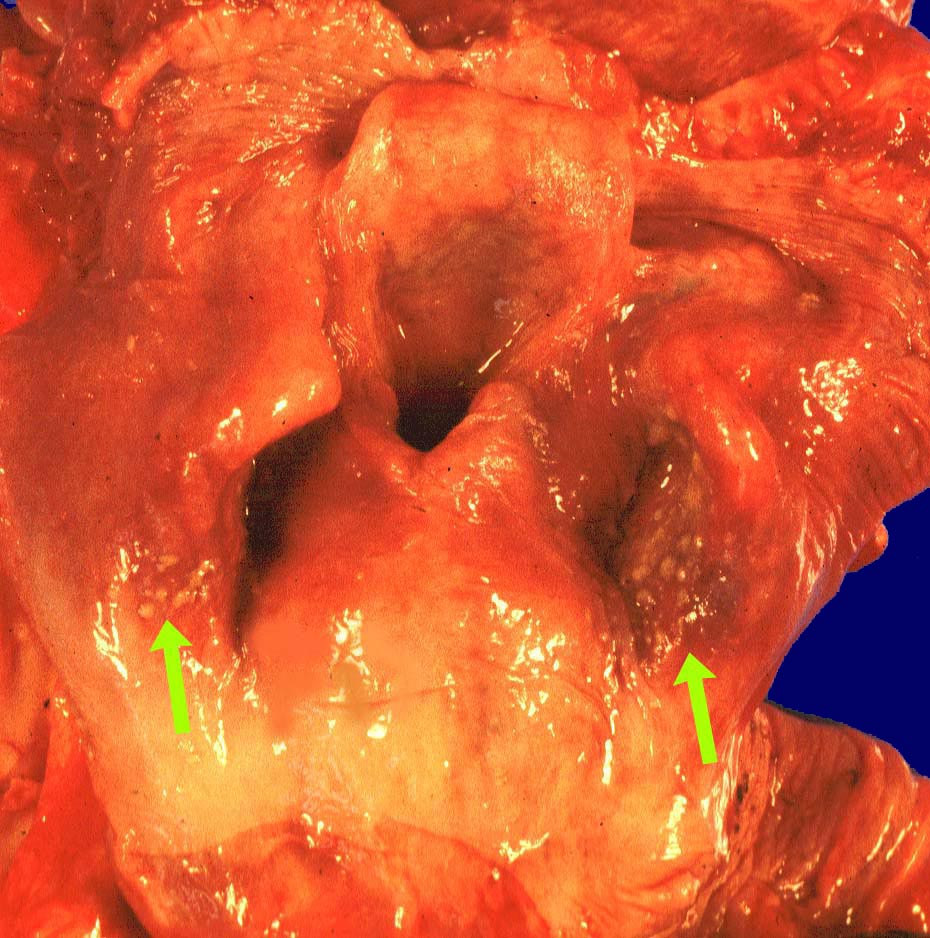

Endoskopisch finden sich abstreifbare weissgelbe krümelige Plaques, welche keine Prädilektionsstelle zeigen. Die Schleimhaut kann erodiert oder ulzeriert sein. In Klumpen von nekrotischen Plattenepithelzellen lassen sich mikroskopisch oft Sporen und Pseudohyphen nachweisen. Die Pseudohyphen wachsen oft senkrecht zur Epitheloberfläche. Besonders gut sichtbar werden die Pilze in der PAS oder Grocott Färbung. Zusätzlich besteht eine aktive Ösophagitis mit Infiltration der oberflächlichen Plattenepithelschicht durch neutrophile Granulozyten. Zahlreiche neutrophile Granulozyten in einem Ulkus weisen auf eine Soorösophagitis. Bei viral bedingten Ulzera (Herpes, CMV) prädominieren Makrophagen.

• Teils ulzerierte, teils erodierte Ösophagusmukosa.